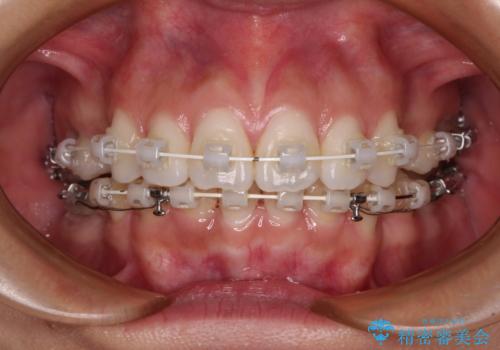

- 口元の突出感を気にして来院された患者様です。

左右ともに奥歯の咬み合わせに問題があり、上顎臼歯が前方位にある状態で、結果として上顎前歯全体が前方位かつ叢生になっていました。

補助装置を用いて上顎歯列全体を後方に移動させ、下顎は左右で抜歯する小臼歯を変えることで、左右の咬み合わせをより理想的な位置となるように計画しました。